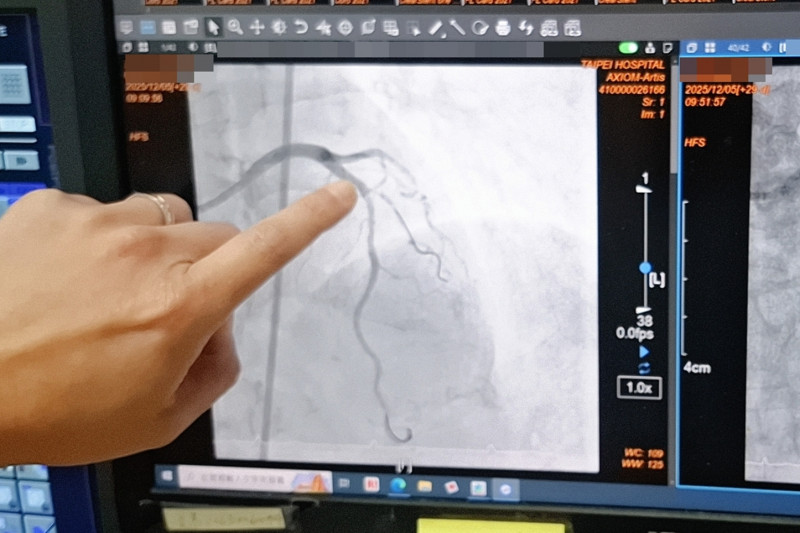

台北醫院表示,1名近80歲的病人近期因胸口不適,檢查發現左前降支的前中段約有80%以上的狹窄病灶,且血管壁存在嚴重鈣化,最狹窄處呈現雙側鈣化,高度疑似環狀型鈣化病灶,屬於傳統氣球擴張成功率低、且血管傷害風險極高的困難病灶,經醫師與病人及家屬說明後,採用血管內震波碎石術,透過高能量震波選擇性擊碎血管壁內鈣化沉積,使血管恢復柔韌度,進而順利完成血管擴張與支架置放,成功完成複雜性高的冠狀動脈介入手術,病人術後恢復情況良好,胸口不適症狀也獲得明顯改善。

台北醫院心臟內科主任黃啟銘說,血管內震波碎石術是革命性的心導管治療方法,醫師透過專屬的球囊導管送入病灶位置,並在低壓下釋放高能量的聲波震動,類似體外碎石治療的概念,能選擇性擊碎血管壁內堅硬的鈣化沉積,讓原本如石頭般堅硬的血管重新變得柔韌,進而安全地完成氣球擴張與支架置放,最大特點在於「精準、低壓、安全」,只針對鈣化病灶發揮作用,避免對正常血管組織造成過度傷害,讓治療變得更為可行與穩定。